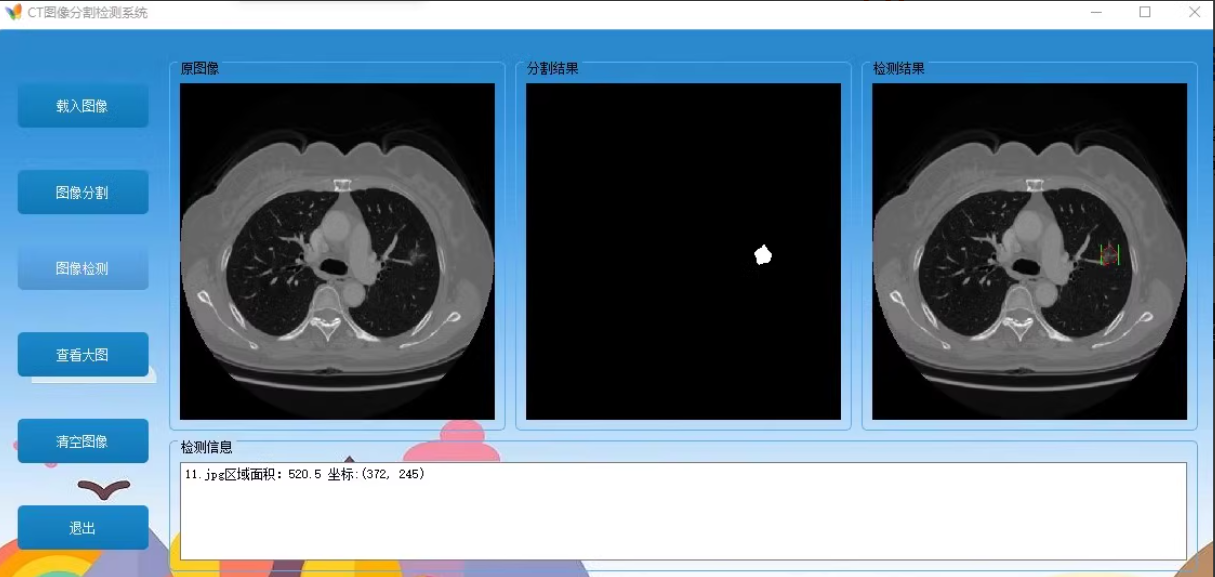

通过python语言 pyqt5界面 建立 基于深度学习的CT医学图像分割检测系统

构建一个CT图像分割检测系统,有那个 登录界面、图像加载、分割和检测功能,使用Python和PyQt5。

通过以上步骤,同学你可以构建一个完整的CT图像分割检测系统,包括登录界面、图像加载、分割和检测功能。